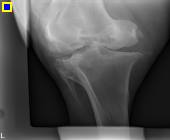

And so we began the X-rays, Pirate understood perfectly well what was going on and stood rock still for over an hour for 15 different X-rays on his stifle, back and neck.

Now here comes the amazing part of Pirates story after going over all the X-rays, from all angles, this was Dr Owens diagnosis. During the car accident, Pirate had suffered a broken neck and a fractured stifle. The amount of pain he must have been in while alone is unthinkable. Through the healing process visible on the pictures, Dr Owen guesses the accident took place approx a year ago. Pirate is a living breathing miracle.

Dr Owen himself said the only way the broken neck had healed was Gods work, that Pirate suffered no neurological damage (in fact quite the opposite) is Gods work. Pirates fractured stifle has healed, and will get stronger as he gets stronger. The body will, eventually heal itself.

Wow, this was a lot to take in. What a brave spirit this boy has!! If he wouldn't give up why should we? If Pirate was a human, he would have a simple knee replacement, being equine, the operation is beyond our financial means and we don't think it would make a huge change for him, the fracture has healed and Pirate is not in demanding work other than to tote a child around occasionally, he does most of his exercise alone bucking and galloping free. The only time Pirate needs meds is a couple of days before the farrier comes for him, this makes it easier for him to lift his leg, and we position him so its comfortable for him.